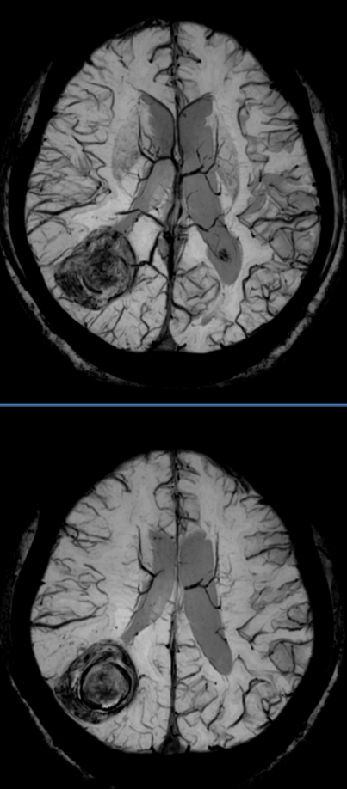

中枢神经系统方向

扩散张量成像(DTI),观察脑白质纤维束的走形、完整性及方向性,可用于描述脑肿瘤与邻近纤维束的关系、观察脑发育等。动脉自旋标记技术(ASL),是一种不打药的血管成像技术,主要作用是用来做磁共振灌注成像。省去了打药的过程,不打药灌注的检查就非常的安全,并且操作方便,便于随访或者复查。采用4D ASL技术,可以不打药(不增强),得到动态的类DSA效果的血管流入流出图像(即4D MRA效果),对于显示血管疾病,特别是Moyamoya、AVM(动静脉畸形)、AVF(动静脉瘘)、血管旁路手术评估、颅内肿瘤血供来源分析等非常有用。磁敏感加权成像(SWI)是一种利用组织间磁敏感性差异及血 氧水平依赖(BOLD)效应成像的磁共振新技术。SWI显示静脉结构、血液代谢产物、矿物质沉积十分敏感,SWI对微出血病灶敏感度更高,在脑肿瘤、脑血管病、脑外伤及神经变性病等中枢神经系统病变中有较高的临床应用价值和广阔的临床应用前景。

磁共振波谱成像(MRS)是目前唯一能无创观察活体组织代谢及生化变化的技术,对脑肿瘤的诊断和鉴别诊断有很大的价值。

SWI